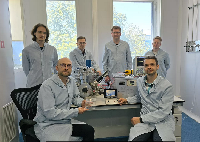

На рабочем месте производится обучение работе на Вашем оборудовании.

Любого доктора можно быстро подготовить как рентгенлаборанта и дать необходимые знания для оценки рентгенограмм.

Изучение проблемы низкого качества рентгенограмм на Вашем оборудовании.